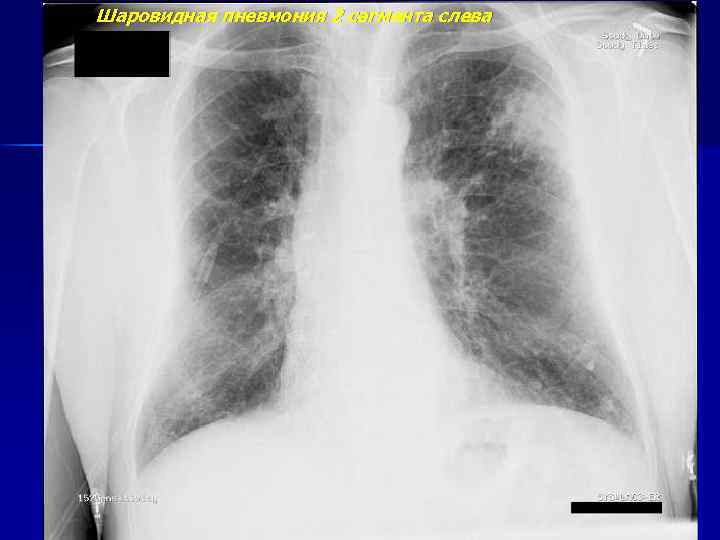

Шаровидная пневмония 2 сегмента слева